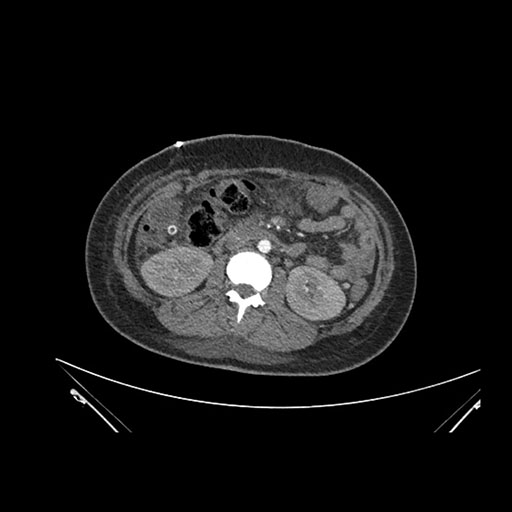

Imaging Analysis

Look through the patient's CT scan to identify any areas of concern for the necessary procedure.

Coronal Venous

Based on initial findings, which issue(s) would you be most concerned about?